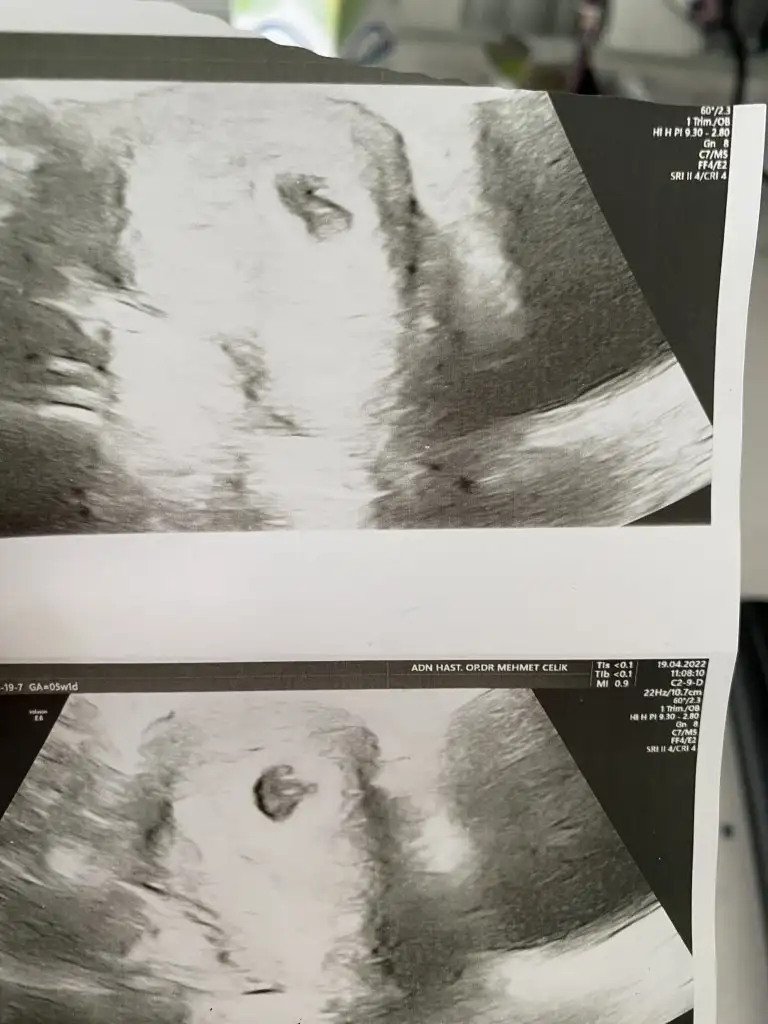

Arkadaşlar Bende kese 4+3te soldaki

5+1 de yani bugün bu şekilde göründü

Biri normal haftasında sanırım 5+1 olan diğeri biraz geride kalmış ama bence korkma zaten ikizlerde hep duyuyoruz ya biri daha iri büyük oluyor diğeri küçük kalıyor bu da onun gibi bence. Ama tabi doktorunuz ve ikiz gebelik geçiren arkadaşlar daha iyi bilir